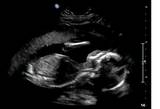

Would love to know your thoughts on our babies gender

The first 3 photo's are from the 19+3 scan. The fourth pic is the 12 week scan.

The second photo is from a different angle (showing both its legs)